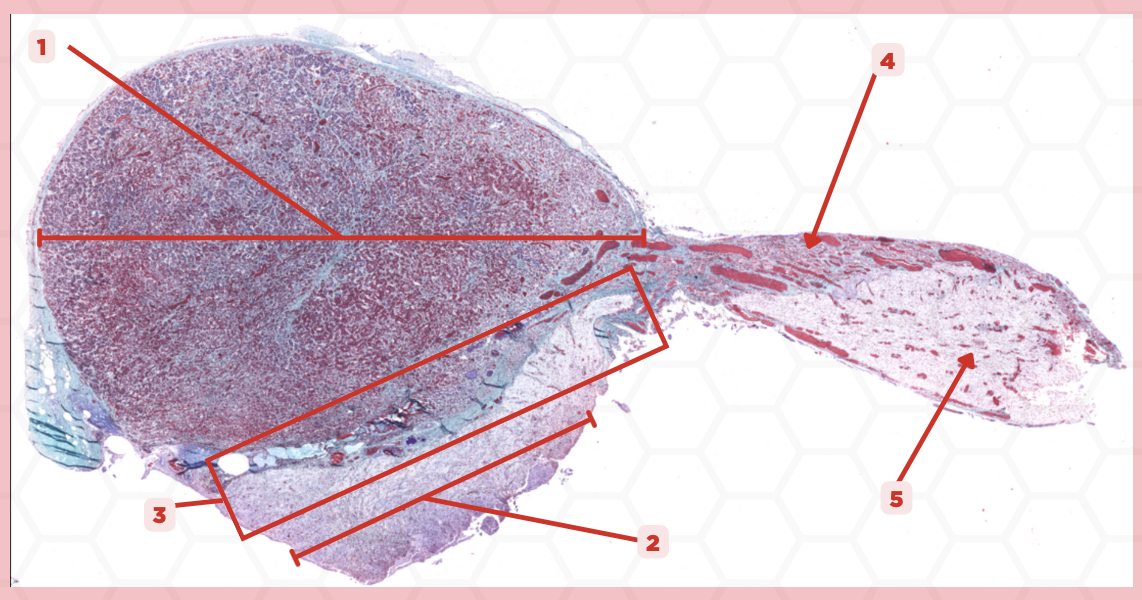

Pituitary

Identify the specimen.

Anterior Lobe

Identify the structure labeled as 1.

Posterior Lobe

Identify the structure labeled as 2.

Intermediate Lobe

Identify the structure labeled as 3.

Pars Tuberalis

Identify the structure labeled as 4.

Pituitary Stalk

Identify the structure labeled as 5.